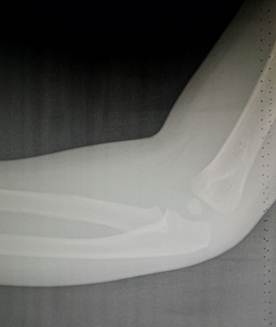

7 лет – 10 лет

В этом возрасте начинается процесс окостенения медиального вала

блока, в котором появляются мелкие, неправильной формы ядра окостенения. В 8

лет появляется ядро окостенения вершины локтевого отростка. Чуть позже к нему

добавляются мелкие ядра - спутники. К концу периода появляется ядро окостенения

латерального надмыщелка.

Возраст 7 лет. Ядро окостенения головчатого возвышения плавно

распространяется в латеральный вал блока и он начинает прослеживаться. Рядом с

ним заметно маленькое линейное ядро окостенения в медиальном вале блока. Появилось два маленьких ядра окостенения

вершины локтевого отростка.